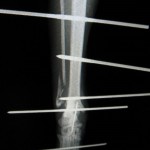

創外固定という器具を用います。

今回は、創外固定ピンと、エポキシ樹脂によって創外固定を作成しました。